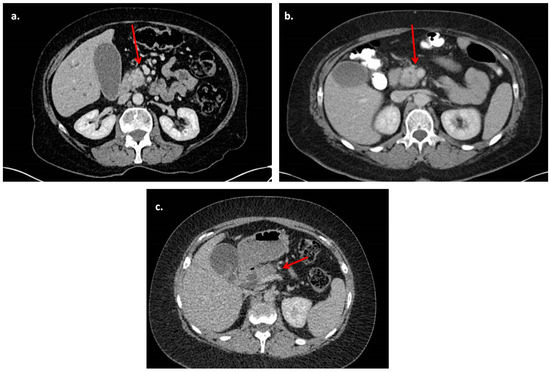

This was a retrospective cohort study conducted in line with STROBE (Strengthening the Reporting of Observational studies in Epidemiology) guidelines [7], following departmental approval at the University Hospitals of Birmingham, a tertiary specialist centre for the treatment of pancreatic cancer. All patients with PDAC who had PD (pylorus-preserving or classical) with or without venous resection were identified from a prospectively maintained database over a 10-year period (2011–2020). Patients with resectable PDAC as per NCCN criteria [3] were included in this study, specifically those with no contact with the vein or contact less than 180 degrees without change in vein wall contour or irregularity. Figure 1 presents examples of venous involvement (Figure 1c is staged as borderline resectable and was not included in this cohort). Patients with ampullary tumours, duodenal cancer, distal cholangiocarcinoma or borderline or locally advanced pancreatic tumours and patients who underwent total pancreatectomy were excluded. Pre-operative staging investigations included CT of the thorax, abdomen and pelvis and endoscopic ultrasound (EUS) with fine-needle aspiration (FNA) when pre-operative cytological diagnosis was required. Magnetic resonance imaging (MRI) and positron emission tomography (PET-CT) were used selectively if there were concerns of metastatic disease based on the CT scan. All cases were referred for adjuvant chemotherapy after surgical treatment and management of all cases was discussed and agreed in hepatopancreaticobiliary (HPB) multidisciplinary meetings. Demographic, clinical and pathological data were obtained from the hospital’s electronic records and the department’s prospectively maintained database. Vein resections were classified according to the system proposed by Tseng et al. [8]. Pre-operative CT images were independently reviewed by two HPB specialist radiologists (WL and SW), who were blinded to the operative, clinical and pathological outcomes. Any conflicts were resolved by further review and discussion with the rest of the authors.

Figure 1.

Representative CT scan images. (a). Resectable pancreatic uncinate process mass with no venous or arterial abutment (arrows). (b). Resectable pancreatic uncinate process mass with abutment of the superior mesenteric vein of <180 degrees and no change in vein wall contour. (c). Borderline resectable pancreatic head mass with compression of the portal vein (case not included in this study).